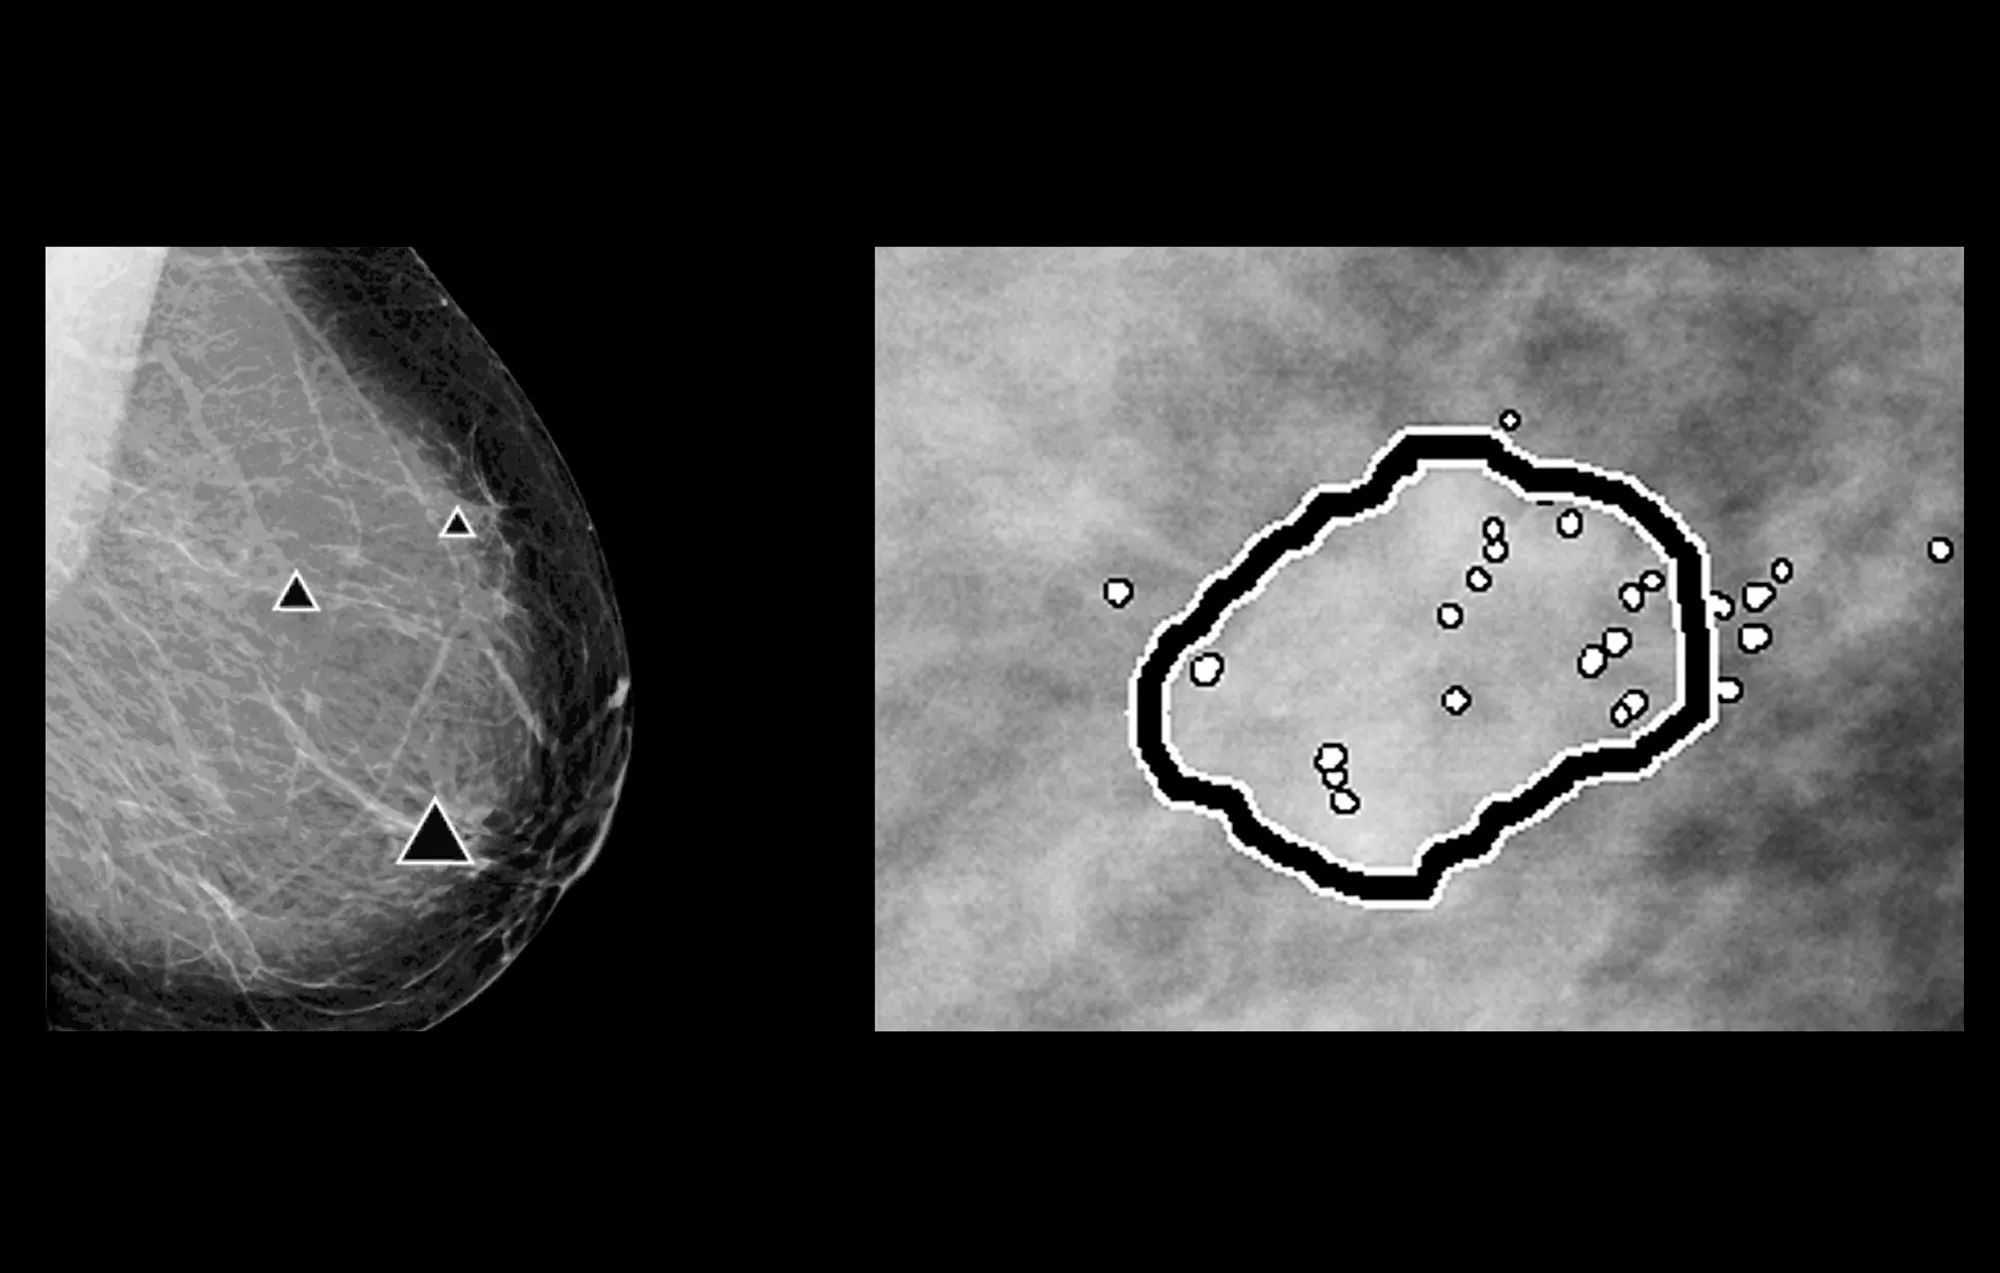

ImageChecker 2D CAD Technology searches digital mammograms for potential microcalcifications and masses, characteristics commonly associated with breast cancer.

• Regions-of-interest are highlighted for the radiologist’s attention

• Delivers highly sensitive results without excessive false-positive marks, streamlining case review2

Digital mammography with peer emphasize marks